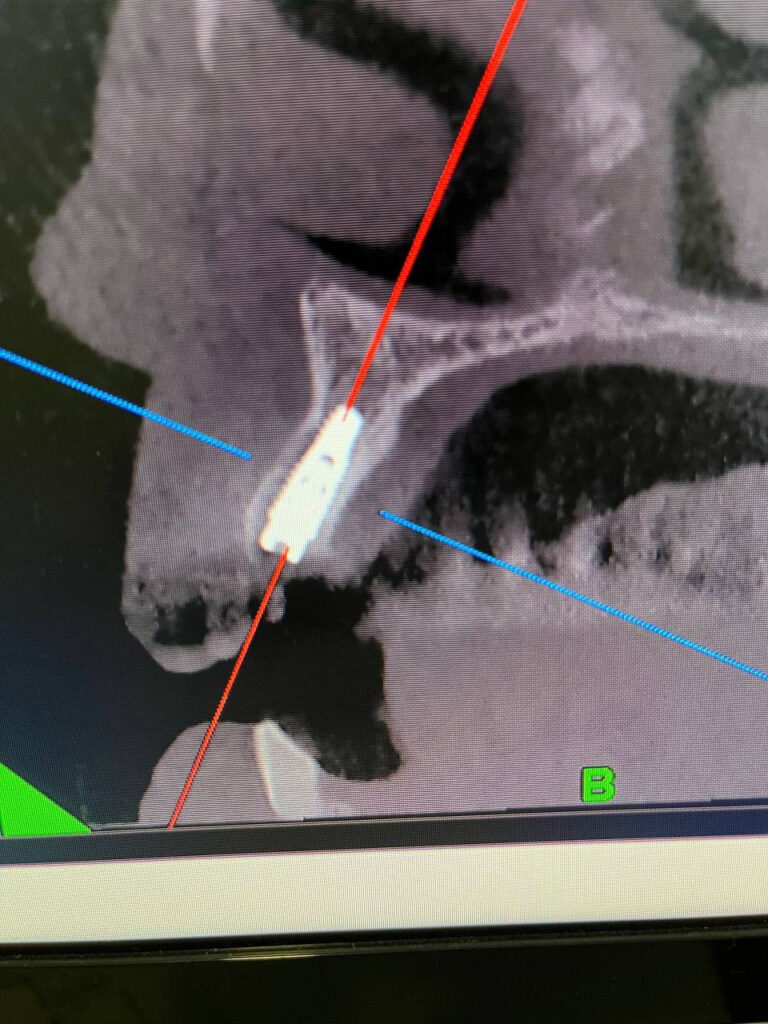

Конусно-лучевая компьютерная томография (КЛКТ) позволяет:

- Видеть кости, нервы, корни и синусы в 3D

- Точно планировать имплантацию

- Находить скрытые проблемы (кисты, воспаления и др.)